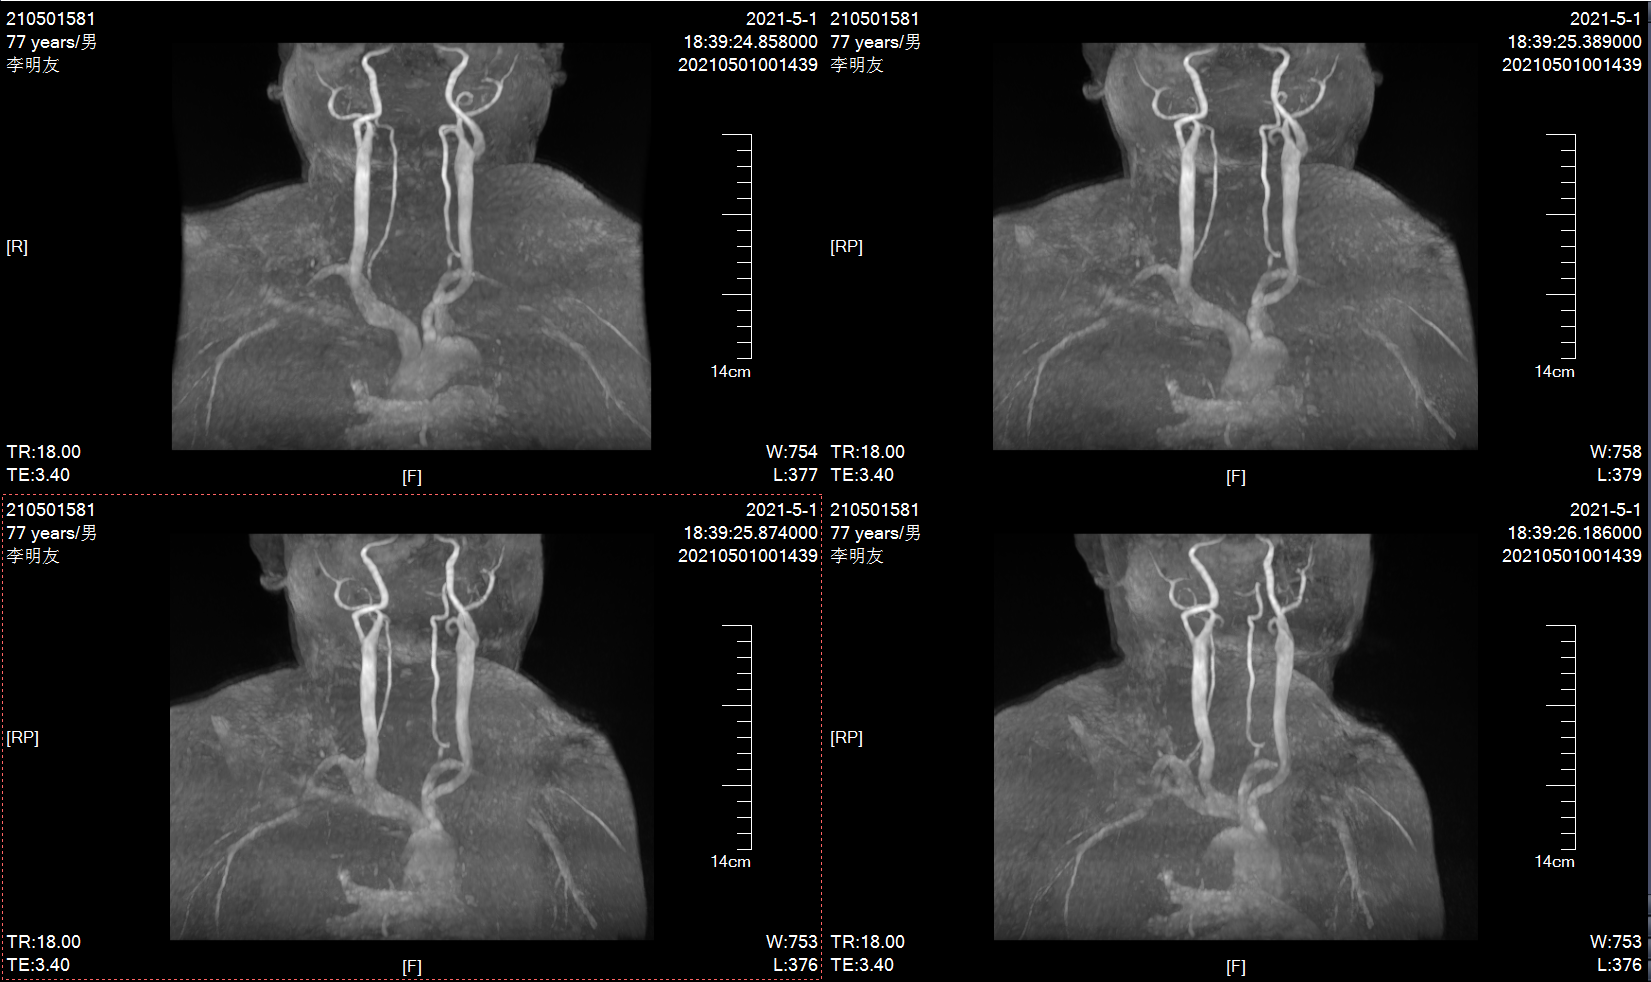

10个月前MRA示左侧颈内动脉轻度狭窄

MRA示左侧颈内动脉重度狭窄